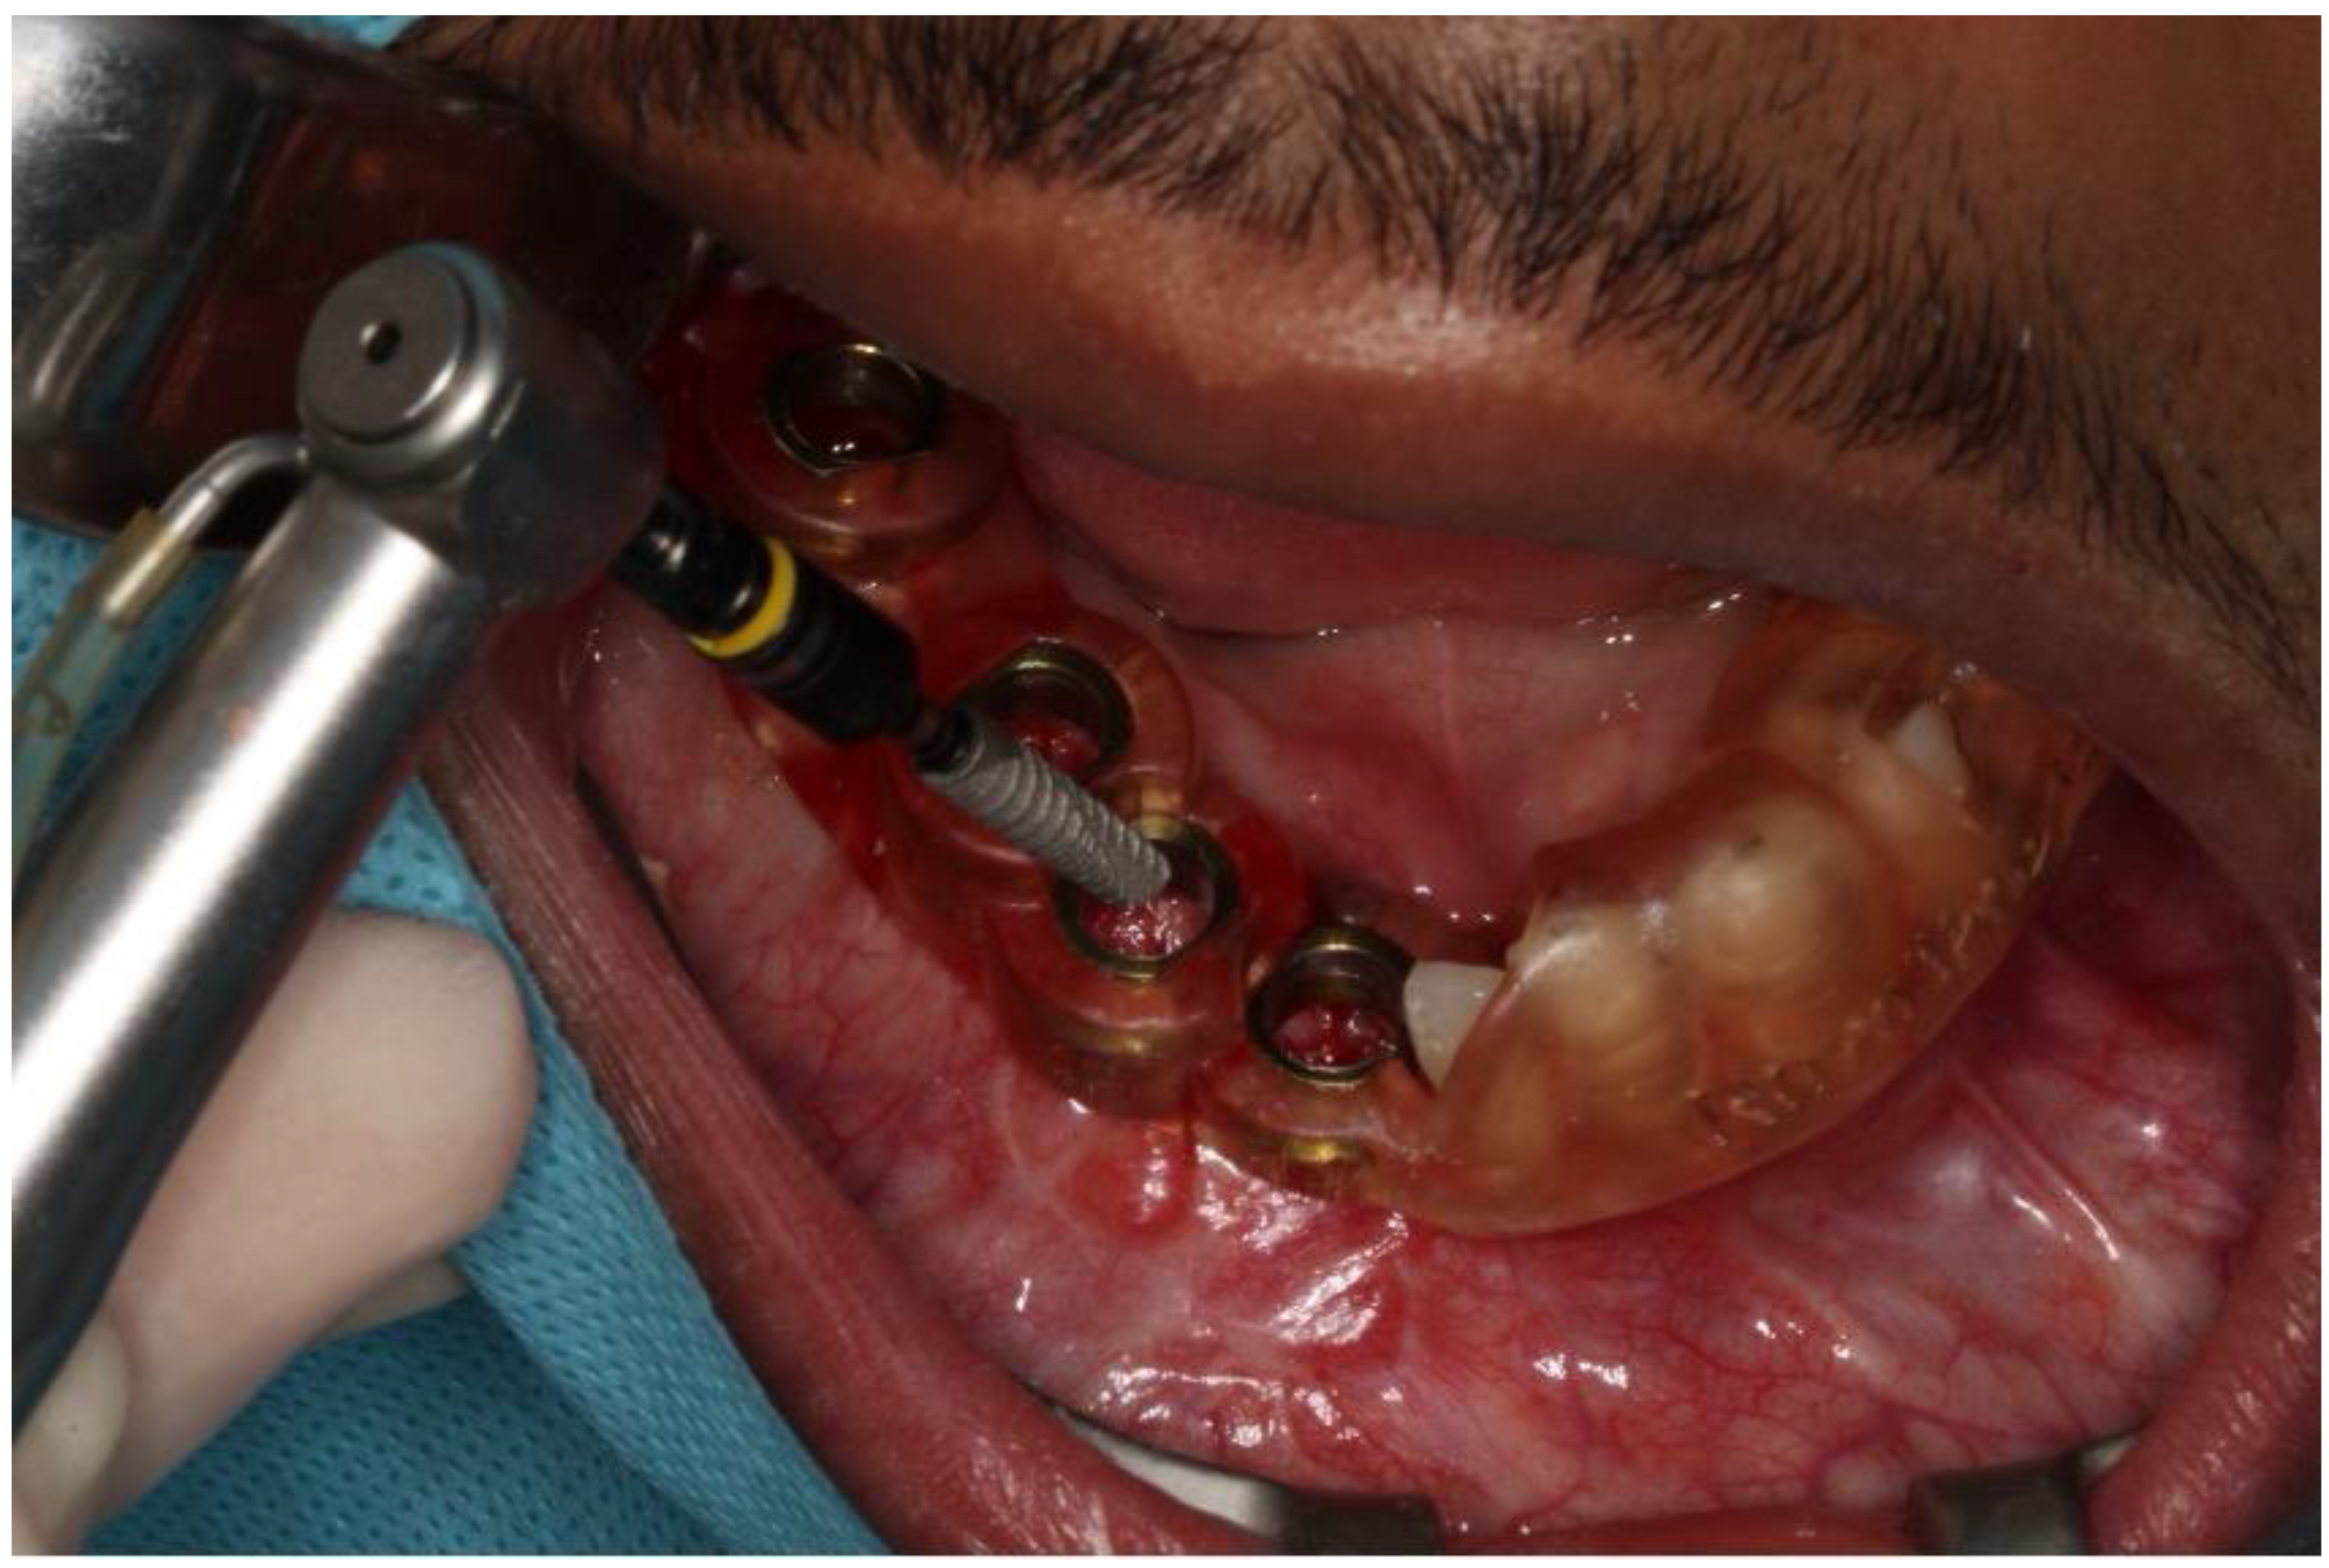

2.1. Case 1